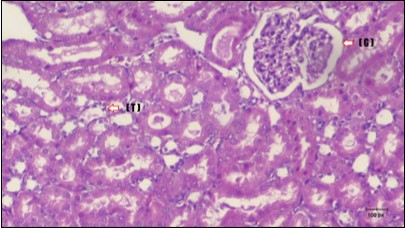

Kidney sections of diabetic rats showed an increase in mesangial cell and matrix of glomeruli with increase in glycogen deposition and hyalinization of arterioles with thickened basement membranes of proximal and distal convoluted tubules. These changes will lead to progressive reduction in the filtration surface of the glomeruli 35. Histological examination of the kidney of the control rats showed normal structure of renal glomerular. The proximal and distal tubules were lined with normal epithelium (Figure 13). The diabetic rats showed tubular casts, inflammatory cellular infiltration and glomerular atrophy (Figure 14). Kidney of rats in groups (3 and 4) showed some glomeruli return to be normal (G). Focal tubules casts (T) in Fenugreek group and some normal tubules in the Glimepiride group with no inflammatory cellular infiltrate in both groups (Figure 15 and Figure 16). However, kidney of rats in group (5) showed normal glomerular (G), normal tubules (T) with no tubular casts (Figure 17).

Figure 15.Photomicrogragh of kidney section of treated rat with Fenugreek showing improvement of Bowman,s capsules with normal glomerular (arrow) and nearly return of distal tubules (dashed –arrow) and proximal tubules (star) (H&E) (40xX).

Figure 16.Photomicrogragh of kidney section of treated rat with Glimepiride showing improvement of Bowman,s capsules and partial improvement of glomerulir (arrow) and completely return of distal tubules and proximal tubules to the normal shape with wide urinary space. (H&E) (40X).